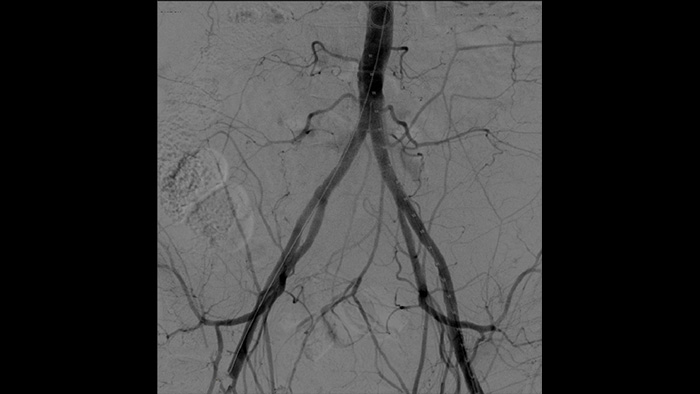

With the Philips Zenition mobile C-arm, Dr. Vila is obtaining outstanding high-quality images that allow him to perform most vascular procedures at the low dose setting.

With the Zenition, our DSA image quality has improved greatly. We no longer see a grainy image. We just see a very clear image."

Vascular processing

Digital subtraction angiography (DSA) is used in interventional vascular procedures to clearly visualise blood vessels by removing structures that can obscure vessel visibility. Roadmap fluoroscopy overlays a previously acquired subtracted contrast image on the live fluoroscopy, allowing you to track a device without reinjecting contrast.